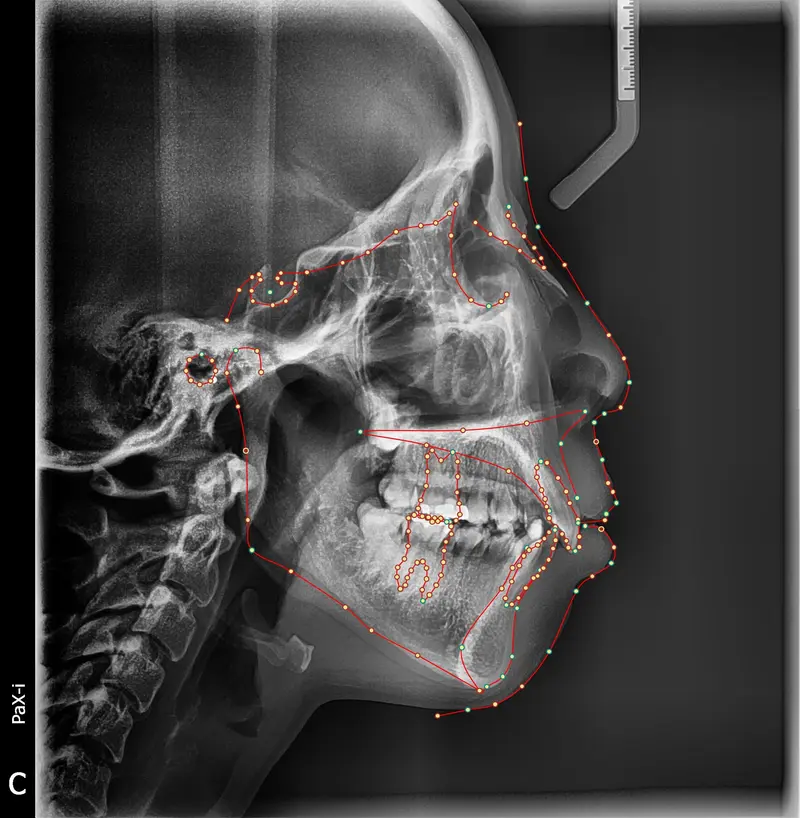

The Diagnosis

Bimaxillary protrusion (teeth flaring forward) causing lip incompetence. The patient struggled to close his lips comfortably, straining the chin muscle (mentalis).

The Engineering

A strategic extraction plan (4 premolars) allowed us to retract the front teeth. Note the dramatic improvement in chin projection and facial balance. The extractions did not flatten the face; they harmonized it.